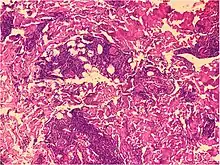

| Kaposi’s sarcoma in patch stage | The patch stage typically shows irregular proliferation of jagged vascular channels in the dermis below an integral epidermis. The so-called promontory sign is sometimes found in patch stage lesions and denotes vascular spaces surrounding pre-existing blood (see image).[23]

vessels |

![]() |